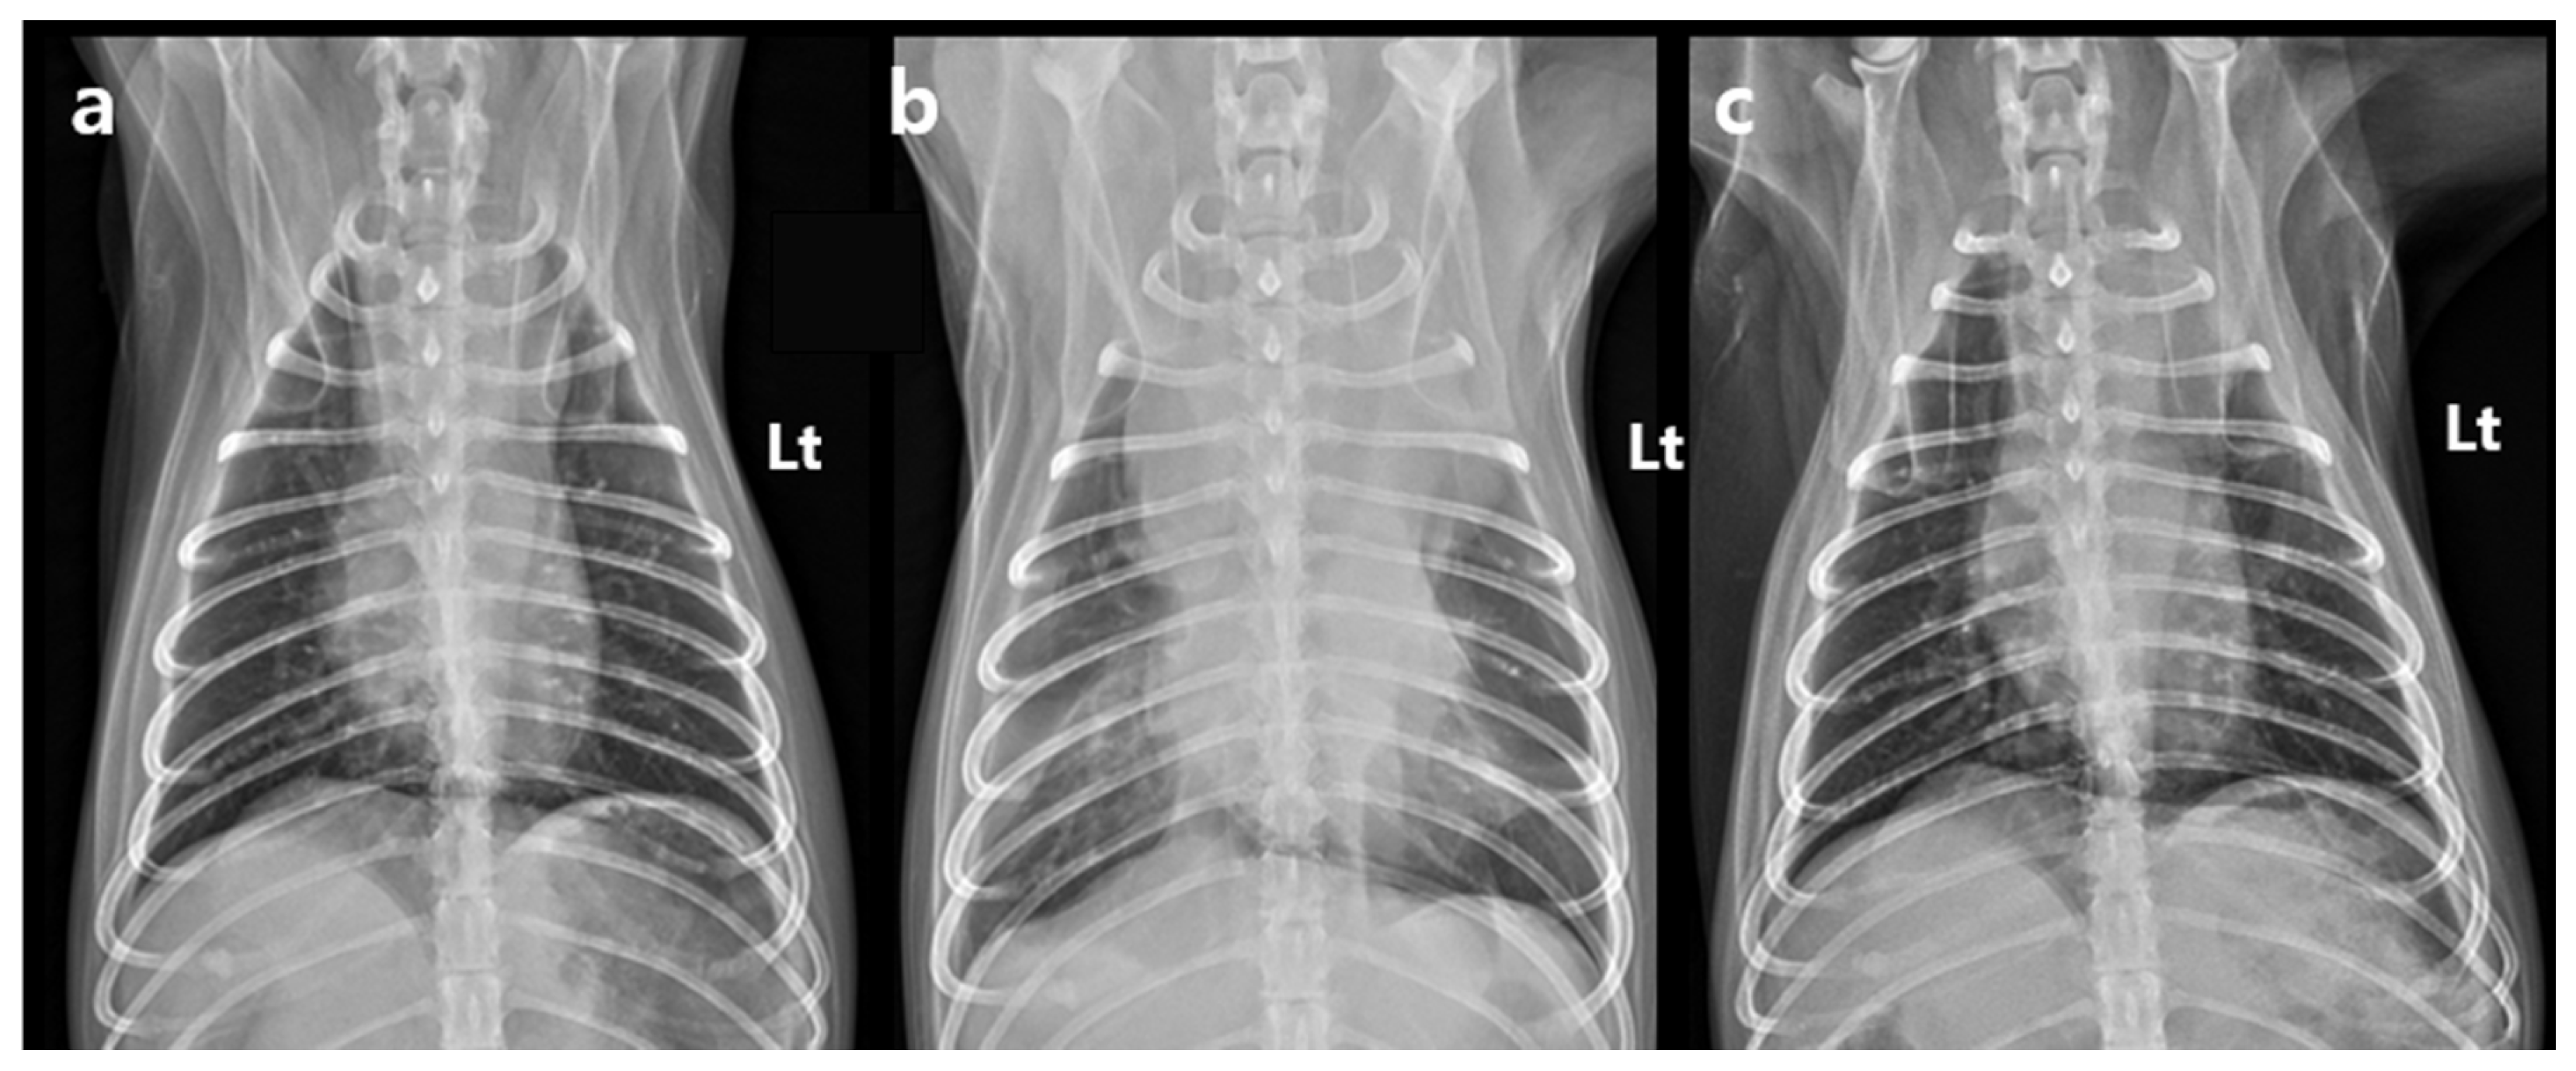

The dog remained clinically stable throughout the SBRT course. The dog completed all three planned SBRT fractions without treatment interruption and remained clinically stable under anesthesia during all sessions. However, the day after the final fraction (5 days after the first fraction), the dog developed acute dyspnea, characterized by increased inspiratory effort and mild open-mouth breathing. Clinical signs of anemia were also evident, as the mucous membranes appeared markedly pale, capillary refill time was prolonged to approximately 2.5 s, and the patient exhibited lethargy with reduced responsiveness to external stimuli. Hematologic testing revealed decreased platelet count (124 × 103/μL), red blood cell count (4.04 × 106/μL), hemoglobin (9.0 g/dL), and hematocrit (28.8%). To rule out an underlying coagulopathy, coagulation testing was performed, and the results showed that PT (10.4 s; reference range: 5–15 s), aPTT (29.2 s; reference range: 15–45 s), and fibrinogen concentration (2.7 g/L; reference range: 1–3 g/L) all remained within normal limits. Thoracic radiographs showed increased cranial mediastinal width (74.5 mm), swelling in submandibular and axillary regions, and pleural effusion (Figure 4). On palpation, the swelling in the bilateral submandibular and axillary regions was cool to the touch, soft, and pitting, with well-defined margins. There was no local warmth, erythema, or pain on palpation. The swelling was symmetrical and corresponded anatomically to the drainage area of the cranial vena cava, suggesting congestion secondary to venous compression rather than inflammatory or neoplastic infiltration. Thoracic ultrasonography revealed a heterogeneous, hypoechoic mass adjacent to the mediastinal lesion, with no detectable vascular flow signals on color Doppler imaging. Transthoracic echocardiography demonstrated a decreased left ventricular internal dimension during both diastole and systole, with preserved global systolic and diastolic function, and no evidence of structural cardiac abnormalities. Anechoic fluid accumulation was observed between the lung parenchyma and thoracic wall, consistent with pleural effusion (Figure 5). Based on the imaging and hematological findings, cranial vena cava compression secondary to tumor-related hemorrhage and hematoma formation associated with the irradiated mass was considered the most likely diagnosis. Other possible differential diagnoses included a necrotic portion of the tumor, abscess formation with inflammation, or a metastatic lesion.

At follow-up, the dog remained in a stable condition, with normal respiratory function and no recurrence of swelling in the submandibular or axillary region. Follow-up CT was performed on day 33 post-SBRT (37 days after the first fraction of SBRT), not primarily to assess tumor shrinkage but rather to evaluate potential treatment-related complications. Specifically, the scan was intended to monitor for tumor-associated hemorrhage and hematoma formation, to assess compression of adjacent vascular and mediastinal structures, and to rule out bleeding from surrounding normal organs. The CT showed an overall increase in tumor dimensions (length: 42.1 mm; width: 49.0 mm; height: 40.0 mm). Tumor volume increased from 25.0 cm3 to 46.4 cm3; however, the contrast-enhancing portion decreased by approximately 25% to 18.7 cm3. This decrease was accompanied by a relative increase in the non-enhancing component of the mass (pre-contrast: 30 HU; post-contrast: 31.5 HU), which exerted compression on the cranial vena cava (Figure 1c,d). Based on imaging features, hematologic findings, and the clinical course, the non-enhancing region was interpreted as a tumor-related hemorrhage secondary to radiation therapy. Thoracic radiography performed on day 88 post-SBRT (92 days after the first fraction of SBRT) revealed a further reduction in the mediastinal width to 43.4 mm, with no evidence of pleural effusion (Figure 4). The dog remained clinically stable, without any evidence of dyspnea, lethargy, or other signs of anemia. At the last follow-up on day 143 after the first SBRT fraction (139 days after completion of the final fraction), the patient was still clinically stable without recurrence of dyspnea or anemia-related signs. Thoracic radiographs at that time showed no significant changes compared with those obtained on day 88 post-SBRT (Figure 4c).

Figure 1. Post-contrast CT images acquired before (a,b) and 37 days after (c,d) the first fraction of stereotactic body radiotherapy. Transverse images are shown in (a,c), and dorsal reconstructions are shown in (b,d). All images were obtained using a soft tissue algorithm (window level, 45; window width, 450). Before stereotactic body radiotherapy, the cranial mediastinal mass displays heterogeneous contrast enhancement and is located in close proximity to the cranial vena cava, right atrium, and right ventricle. CT performed 37 days after the first radiation fraction shows that the overall size of the mass has increased; however, the volume of the contrast-enhancing region has decreased by approximately 25%. The cranial vena cava is compressed by a newly developed non-enhancing region (white arrow). CT, computed tomography. Lt: left.